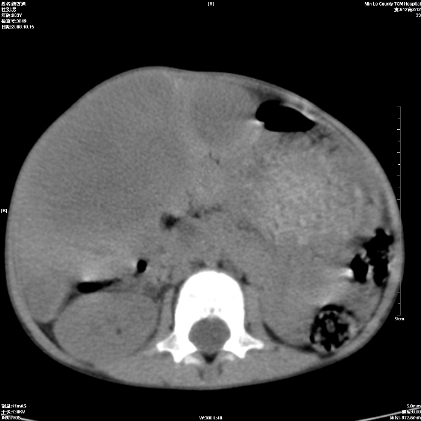

标题: PED1609:男性,3岁。彩超示肝Ca. [打印本页]

标题: PED1609:男性,3岁。彩超示肝Ca.

3岁;肝低密度灶;有钙化;有转移灶;考虑肝母细胞瘤;查afp

考虑:1、右侧后下纵隔畸胎瘤。

2、肝脏多发血管内皮细胞瘤。

建议:增强确诊。